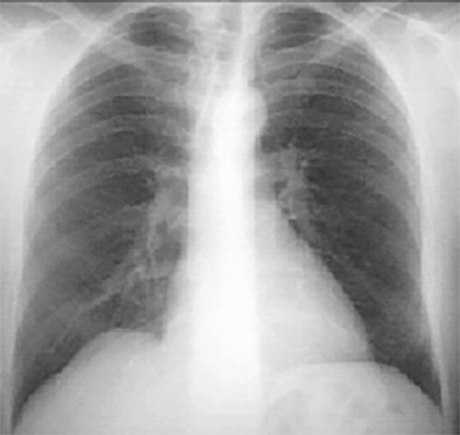

PA and Lateral

Click on the Xrays to enlarge them.

Choose the best interpretation of the chest X rays:

Normal with straight back syndrome

Normal

Dilated ascending aorta

Normal with bilateral accessory rib

Calcified coronary arteries